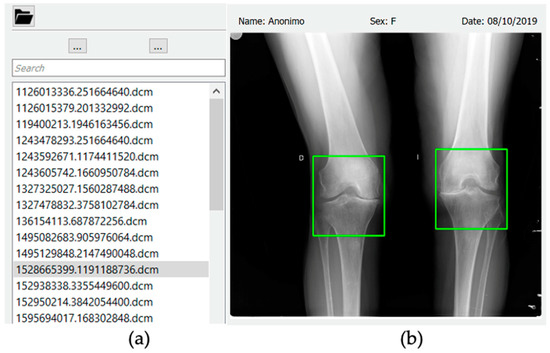

3.3. Classification and User Interface